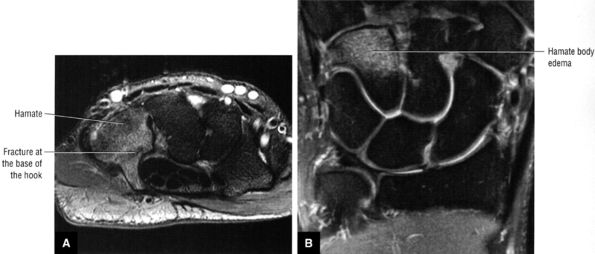

|